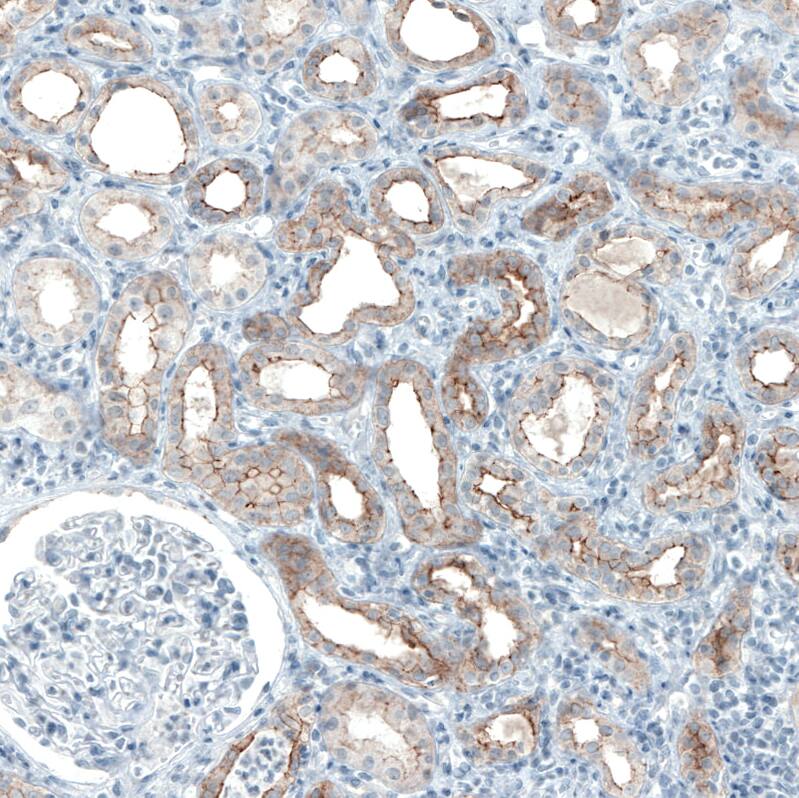

Staining of human kidney shows moderate to strong positivity in apical membrane in cells in tubules.